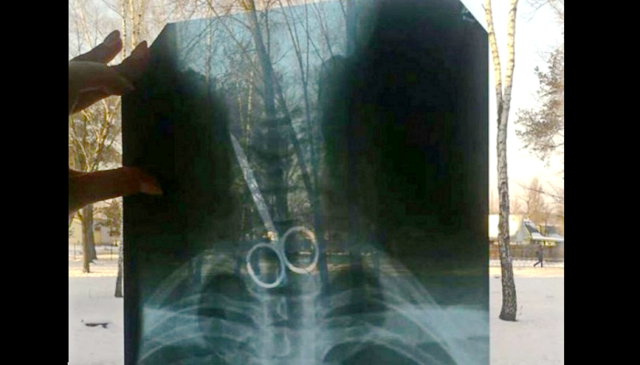

К врачам Черниговской областной больницы обратился местный житель с просьбой осмотреть его. Медики сделали рентген, который показал, что в желудке пациента находятся металлические предметы - ножницы и ложка.

Сейчас имя и возраст мужчины не разглашаются. Однако, стало известно мотив такого поступка. Так, черниговец проглотил предметы на спор.